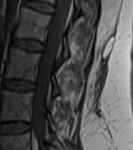

Resim 1. Sagital T1 ve T2 ağırlıklı lomber MR görüntülerinde subkutan doku ile torakolomber fasiyal planlar arasında psödokapsüllü sıvı toplanması izlenmekte (Morel-Lavallée lezyonu).